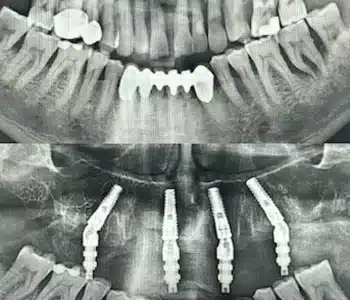

Dr. Seden Aksu is a specialist in modern implantology and surgical dentistry with extensive experience in the management of complex clinical cases. In her practice, she applies comprehensive surgical planning, minimally invasive techniques, and advanced regenerative technologies aimed at restoring both the function of the dentoalveolar system and the aesthetics of the smile. Dr. Aksu has significant experience in performing implant procedures, bone augmentation, and periodontal surgery, including the treatment of patients with severe bone loss. The primary goal of her work is to achieve stable, long-term outcomes in implant rehabilitation and the restoration of oral tissue health.